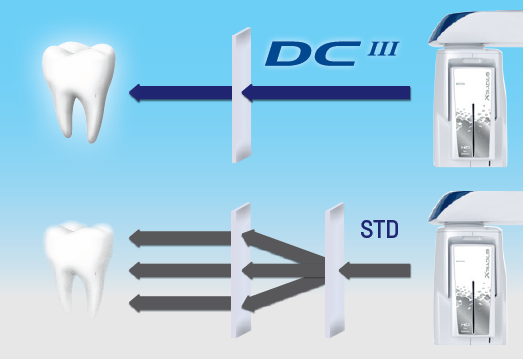

Датчик прямого преобразования (DCD)

Преобразовываясь напрямую в электрические сигналы, минуя стадию преобразования в свет, рентгеновские фотоны остаются в неизменном виде до тех пор, пока не сформируют панорамное изображение. Таким образом благодаря минимальному рассеиванию сигнала технология позволяет генерировать значительно более четкие изображения, чем те, которые получены с использованием традиционной технологии. Это гарантирует высококонтрастные экстраоральные 2D-снимки при низких дозах облучения: панорамные изображения и телерентгенограммы, визуализацию верхнечелюстных пазух, ВНЧС, зубных рядов и прикуса.